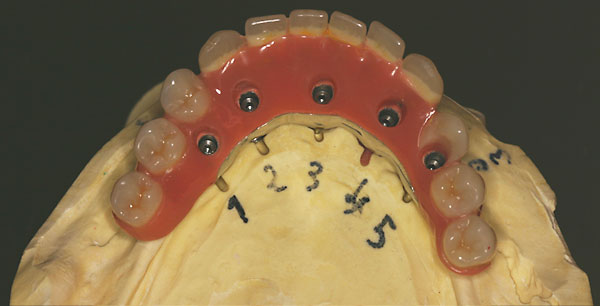

Fall: festsitzender Zahnersatz im Oberkiefer auf 8 Implantaten

FOTO Meistermodell mit Laborimplantaten zur Herstellung der Brücken |

FOTO vier kleine Brückensegmente ergeben die Oberkieferversorgung |